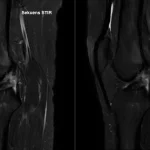

Studi Komparasi Sekuens T2 STIR dan T2 SPAIR pada MRI Lutut Kasus Rupture ACL